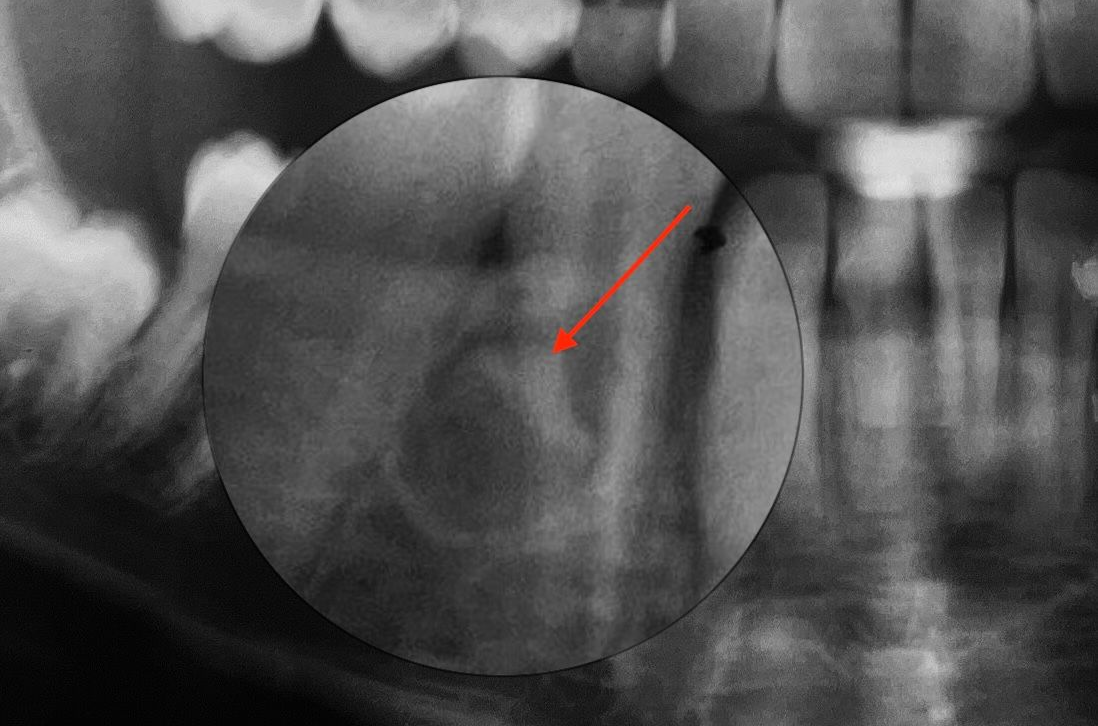

Visione radiografica

Visione post estrattiva